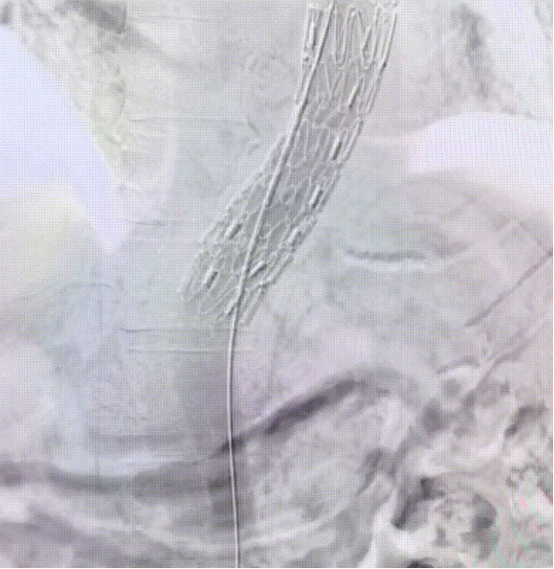

远端置入裸支架

病人平卧DSA手木床,常规消毒铺巾,局麻,分别穿刺右侧桡动脉、左侧股动脉。经右桡动脉导入5F PIG造影导管至主动脉弓行主动脉造影提示破口位于左侧锁骨下动脉开口后缘,夹层累及至右髂外动脉。左侧股动脉预埋2把血管缝合器,交换22F动脉鞘,沿加硬导丝通路送入胸主内嵌覆膜支架系统至主动脉弓部精确定位,将开窗与LSA平齐,释放主体支架,复查造影示支架贴壁良好、无内漏,LSA通畅未受累,再送分支支架系统释放,复查造影示支架定位准确,LSA开口稍受限,遂送入10*60m外周球囊扩张LSA开口,复查造影示支架塑形良好,分支通畅、无内漏,效果满意。沿导丝送入金属裸支架至降主动脉段衔接主体支架后释放,复查造影示支架贴壁良好,无内漏,分支无受累缝合左侧股动脉,手术过程顺利,术后患者安返病房。